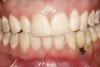

Figure 6  Mucogingival and residual defect after removal of implant in site No. 22.

Figure 6

The patient had no medical concerns and had a history of an implant placement in December 2002 when she was 25 years old. In February 2005, she presented with a mobile implant and an associated advanced peri-implantitis. Radiographic review at the initial examination demonstrated significant destruction of the dentoalveolar ridge around the implant as well as around the adjacent natural dentition. Emergency-based treatment involved surgical implant removal only and debridement of the infection (Figure 4 and Figure 5). Following uneventful healing, an advanced ridge defect was apparent at the edentulous site and moderate and advanced attachment loss noted at No. 22D and No. 21M, respectively (Figure 6 and Figure 7). This case demonstrates bone loss of two separate origins: lack of bone because of tooth agenesis and destruction of bone from inflammatory peri-implantitis.